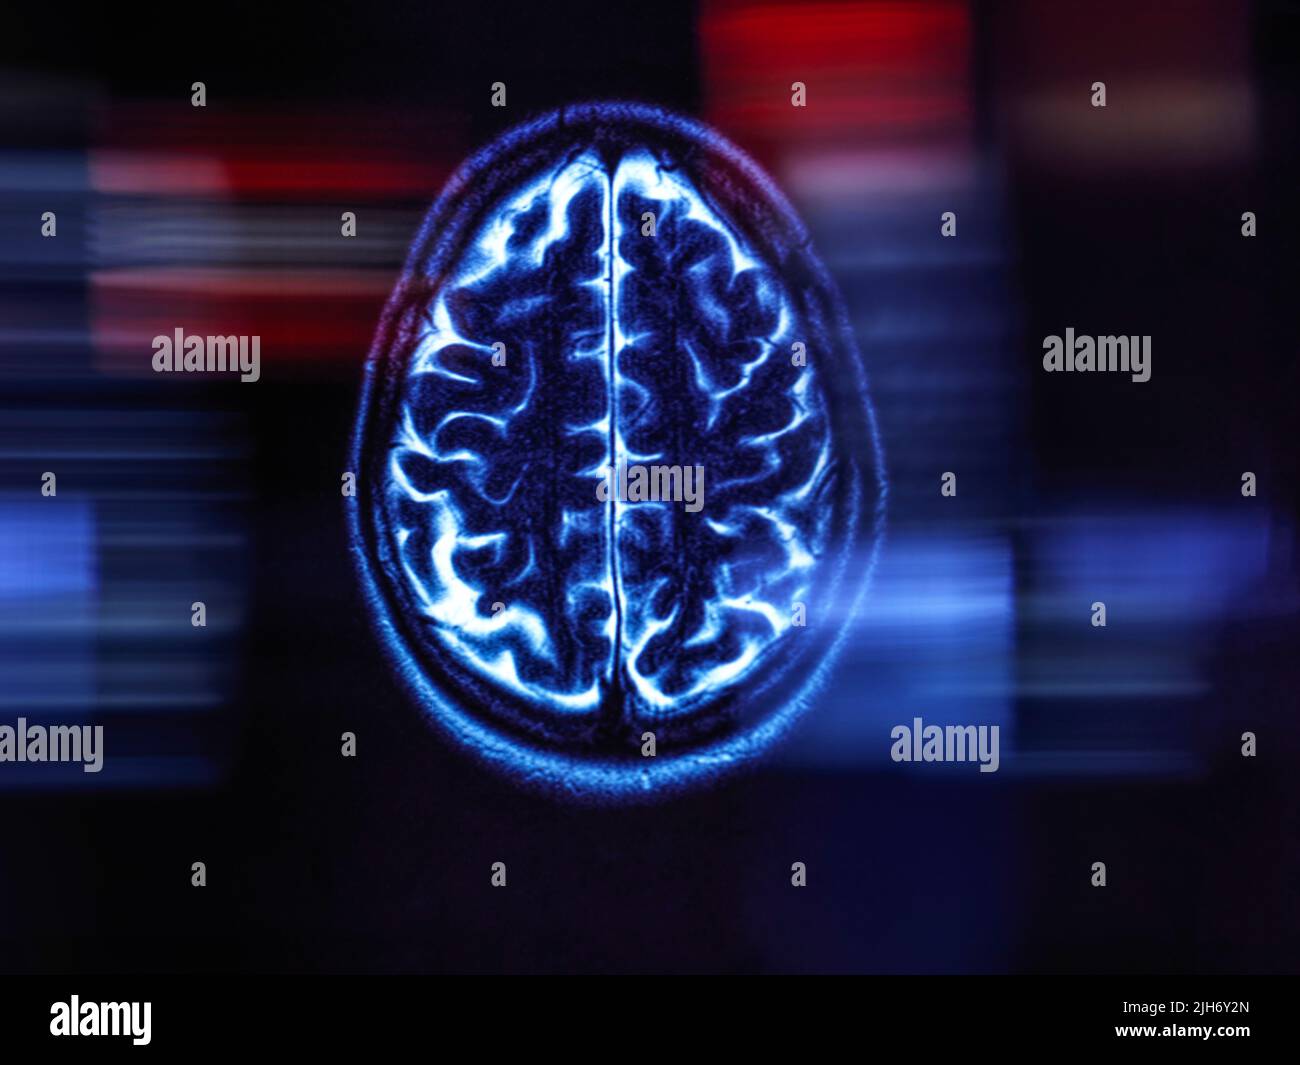

Alzheimer's and dementia research, conceptual image Stock Photohttps://www.alamy.com/image-license-details/?v=1https://www.alamy.com/alzheimers-and-dementia-research-conceptual-image-image475282043.html

Alzheimer's and dementia research, conceptual image Stock Photohttps://www.alamy.com/image-license-details/?v=1https://www.alamy.com/alzheimers-and-dementia-research-conceptual-image-image475282043.htmlRF2JH6Y2K–Alzheimer's and dementia research, conceptual image

Alzheimer's and dementia research, conceptual image Stock Photohttps://www.alamy.com/image-license-details/?v=1https://www.alamy.com/alzheimers-and-dementia-research-conceptual-image-image475282013.html

Alzheimer's and dementia research, conceptual image Stock Photohttps://www.alamy.com/image-license-details/?v=1https://www.alamy.com/alzheimers-and-dementia-research-conceptual-image-image475282013.htmlRF2JH6Y1H–Alzheimer's and dementia research, conceptual image

Alzheimer's and dementia research, conceptual image Stock Photohttps://www.alamy.com/image-license-details/?v=1https://www.alamy.com/alzheimers-and-dementia-research-conceptual-image-image475282045.html

Alzheimer's and dementia research, conceptual image Stock Photohttps://www.alamy.com/image-license-details/?v=1https://www.alamy.com/alzheimers-and-dementia-research-conceptual-image-image475282045.htmlRF2JH6Y2N–Alzheimer's and dementia research, conceptual image

Alzheimer's and dementia research, conceptual image Stock Photohttps://www.alamy.com/image-license-details/?v=1https://www.alamy.com/alzheimers-and-dementia-research-conceptual-image-image475282040.html

Alzheimer's and dementia research, conceptual image Stock Photohttps://www.alamy.com/image-license-details/?v=1https://www.alamy.com/alzheimers-and-dementia-research-conceptual-image-image475282040.htmlRF2JH6Y2G–Alzheimer's and dementia research, conceptual image